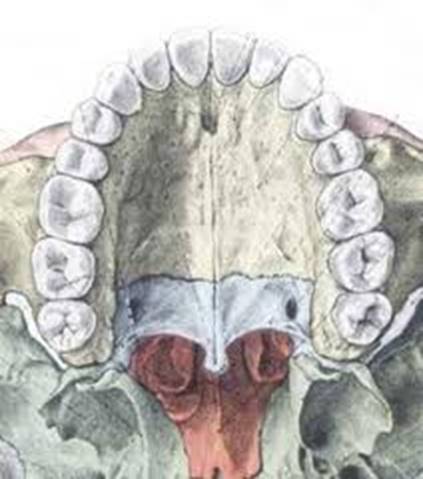

Tissues and organs of the embryo, which morphologically starts to look like a human, develop from three layers, which are called the ectoderm, mesoderm, and endoderm. While the baby continues to come to life inside the mother’s womb, the cranial and facial regions, along with oral cavity, start to form via the development of cells in the area called the neural crest. This development is the result of perfectly corresponding functions in between the epithelium and outer mesenchyme, which results in the facial skeleton and formation of teeth.

Jaw and facial development occur during the 4-12 weeks in the womb. By the end of the 10th week, the face can be seen with an ultrasonographic examination.

The nose forms at this point. Mid and lateral nose projections develop. A forehead projection called the “frontonasal protrusion” forms in between the two sided mid nose projections. These projections initially develop towards the lower direction because of the volume of the tongue. Later, after the palate has begun to form, and with the growth of the lower jaw and the downward extension of the tongue, like an open-close bridge, the lower and upper jaw join at the midline by rising upward. This union takes place from front to back, like closing a zipper, stage by stage.

This way, the oral cavity and the surrounding structures (tongue, teeth, etc.) that will enable speech and taste are knit, loop by loop, inside the mother’s womb. (Figure 1-2)

Figure-2: Upper jaw bone